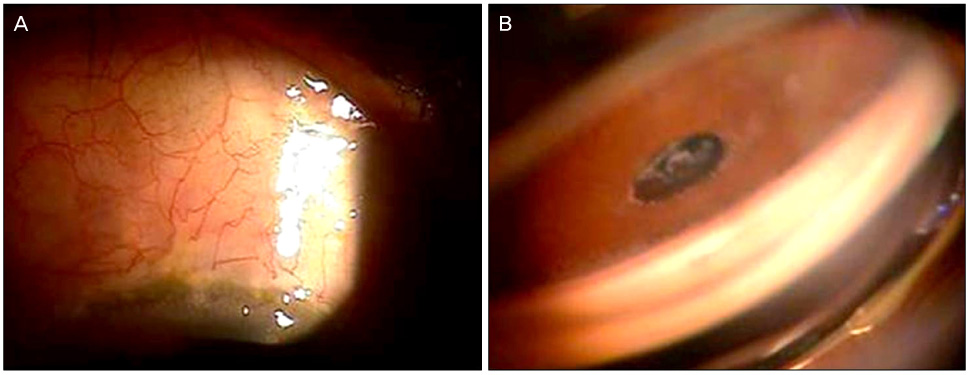

섬모체해리 틈새 (cyclodialysis cleft)

섬모체해리 틈새란 섬모체가 섬모체가 붙어있어야하는 공막부위로부터 떨어지는 것을 말합니다.

이는 홍채절제술을 할 때 과도하게 당기게 되면서 홍채와 붙어 있는 섬모체가 당겨지면서

공막부위로부터 떨어지는 경우가 가장 흔합니다.

섬모체는 안구내에서 방수생성을 담당하는 위치인데, 섬모체 해리가 발생하게되면,

해당부위의 섬모체는 기능을 잃어 저안압이 빠지거나,

섬모체로부터 방수의 흐름이 비정상적으로 흘러들어가, 섬모체와 공막사이 공간 혹은 맥락막과 공막사이의 공간(suprachoroidal space)에 고이게 되면서 이차적인 문제를 발생시킵니다.